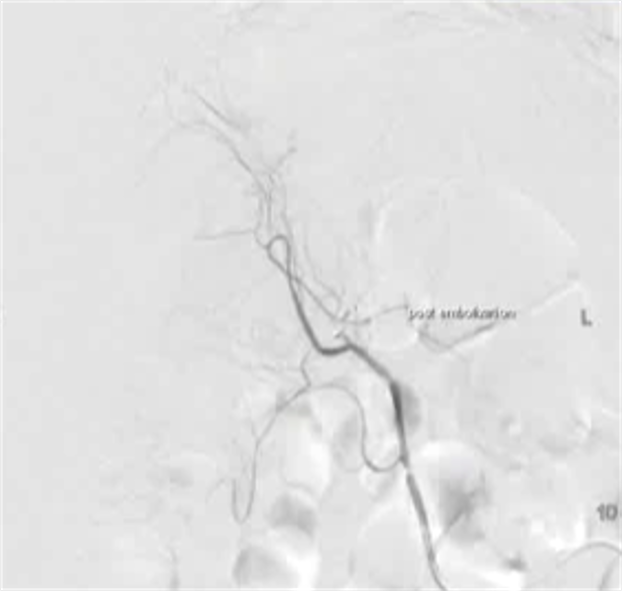

病例二

100/50 mmHg

20 μց Arterenol 170/80 mmHg

病例3 80/50 mmHg

40 μg Arterenol 170/90mmHg

|

出血点, |

PVA栓塞 |